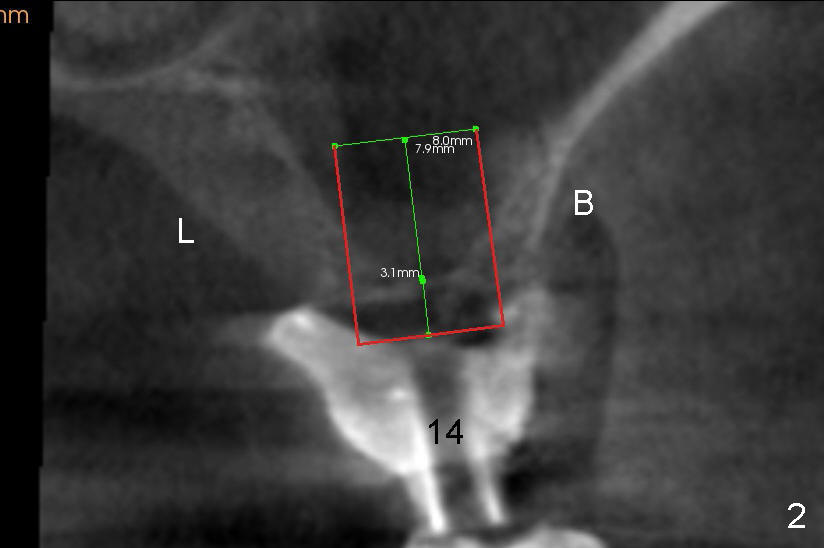

The two cases we discuss early appear to show that implants at the first molar are placed to engage in the mesial aspect of bone to have primary stability (1,2). But sometimes sinus floor may be right above the first molar (Fig.1-4). Fig.1 (CT sagittal) and 2 (coronal) were taken before #15 extraction, whereas Fig.3, 4 (PA) were taken during and immediately after extraction, respectively. A tapered 8x17 mm implant was placed at the site of #15.

In order to get primary stability, it is apparent that a large screw implant should be placed (Fig.1,2: 8x11 mm) to engage all of the lateral walls of the concave sinus floor (mesial and distal (Fig.1), buccal and lingual (Fig.2 B, L). Three millimeter shorter implant may be more appropriate (8x8 mm) in term of being less traumatic.